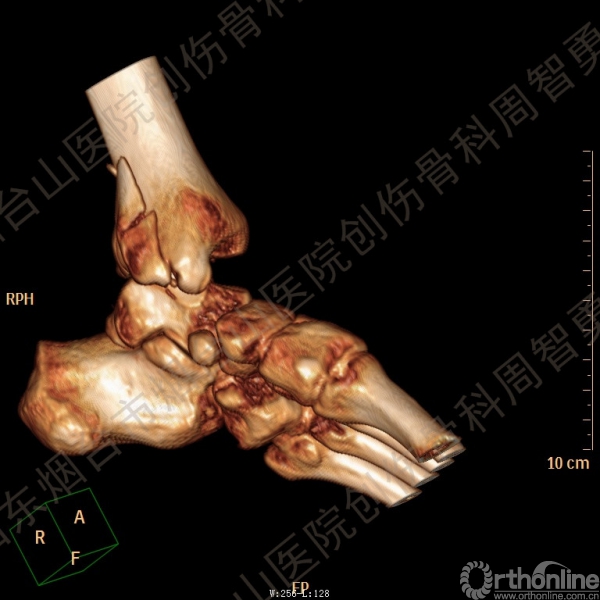

患者一般情况可,左踝关节肿胀,见皮下瘀斑,内、外、后侧有压痛,左踝关节主动运动受限,左足皮肤感觉、血供未见明显异常,左足趾各关节可主动运动。左踝关节正位X线片和CT重建示内踝内上方双层骨皮质影(图1a,c),CT示后侧骨折块分为后内侧骨折块和后外侧骨折块(图2a,b),后内侧骨折块累及内踝后丘,后丘骨折线呈冠状位(图2c),后内侧骨折块腹侧有向近端塌陷的小块骨软骨骨折块(图2d),CT也显示Chaput骨折块(图1c,2e)。

经典的后踝骨折发生于低能量旋转外力所致的踝关节骨折;标准pilon骨折见于高能量轴向暴力;而后侧pilon骨折是旋转外力和轴向暴力共同作用的结果,属于中等能量的损伤。踝关节骨折中的后踝骨折源自下胫腓后韧带的牵拉,骨折块位于后外侧,常为单一的三角形骨折块,大小从关节外片状骨折到累及胫骨远端关节面矢状径的40%(图4a)。后侧pilon骨折中的后侧骨折块较大,累及内踝后丘(三角韧带深层起点)在内的整个胫骨远端后侧,分为后内侧骨折块和后外侧骨折块,后内侧骨折块腹侧有向近端塌陷的骨软骨骨折块(图4b)。后侧pilon骨折中的内踝骨折线并不是水平位而是冠状位,可合并内踝前丘骨折。后侧pilon骨折踝关节正位X线片示特异性的内踝内上方双层骨皮质影(图1a,c)。这是由于后内侧骨折块的骨折线延伸到胫骨远端骨骺和干骺端的内侧骨皮质,其移位后的边缘成像所致。水平位CT显示后侧骨折块分为后内侧骨折块和后外侧骨折块,矢状位CT示后内侧骨折块腹侧有向近端塌陷的骨软骨骨折块。

↑ 图 2a

↑ 图 2b

↑ 图 2c

↑ 图 2d

↑ 图 2e

图 2 术前CT,显示后侧骨折块分为后内侧骨折块和后外侧骨折块(a,b),后内侧骨折块累及内踝后丘,后丘骨折线呈冠状位(c),箭头所示后内侧骨折块腹侧有向近端塌陷的小块骨软骨骨折块(d),Chaput骨折块(e)